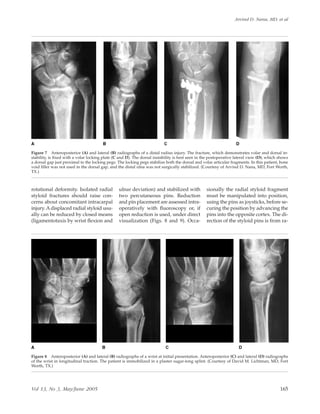

Figure 7 Anteroposterior (A) and lateral (B) radiographs of a distal radius injury. The fracture, which demonstrates volar and dorsal in-

stability, is fixed with a volar locking plate (C and D). The dorsal instability is best seen in the postoperative lateral view (D), which shows

a dorsal gap just proximal to the locking pegs. The locking pegs stabilize both the dorsal and volar articular fragments. In this patient, bone

void filler was not used in the dorsal gap, and the distal ulna was not surgically stabilized. (Courtesy of Arvind D. Nana, MD, Fort Worth,

TX.)

Figure 8 Anteroposterior (A) and lateral (B) radiographs of a wrist at initial presentation. Anteroposterior (C) and lateral (D) radiographs

of the wrist in longitudinal traction. The patient is immobilized in a plaster sugar-tong splint. (Courtesy of David M. Lichtman, MD, Fort

Worth, TX.)